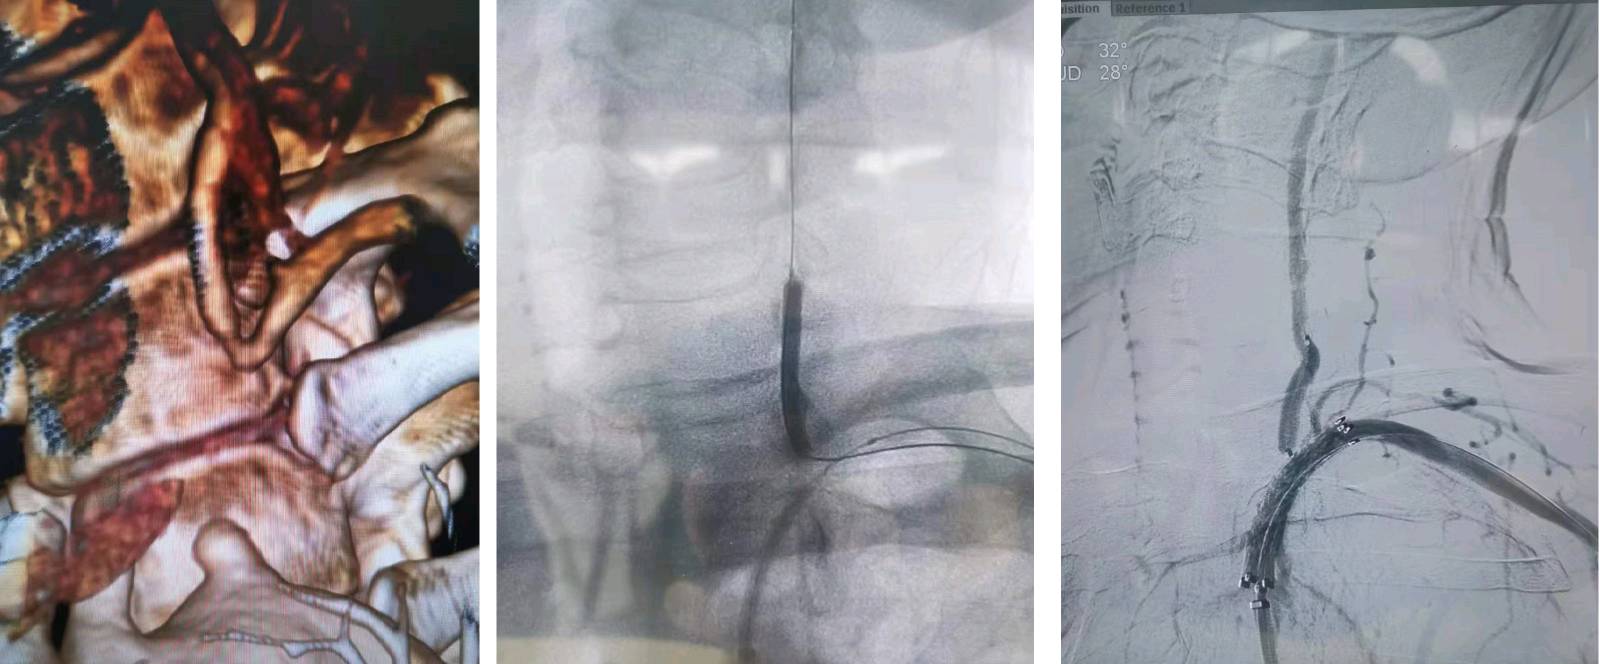

分享本周弓上动脉,左椎动脉保护下行左锁骨下动脉支架植入术。

左锁骨下动脉长段病变,小球囊通过左侧肱动脉入路实现左椎保护,裸支架完全覆盖病变。